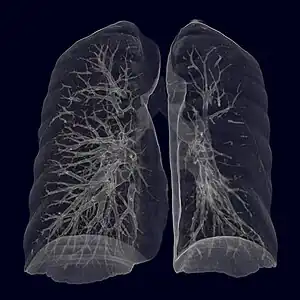

| Swyer–James syndrome of the left (smaller) lung, virtual CT-bronchography. | |